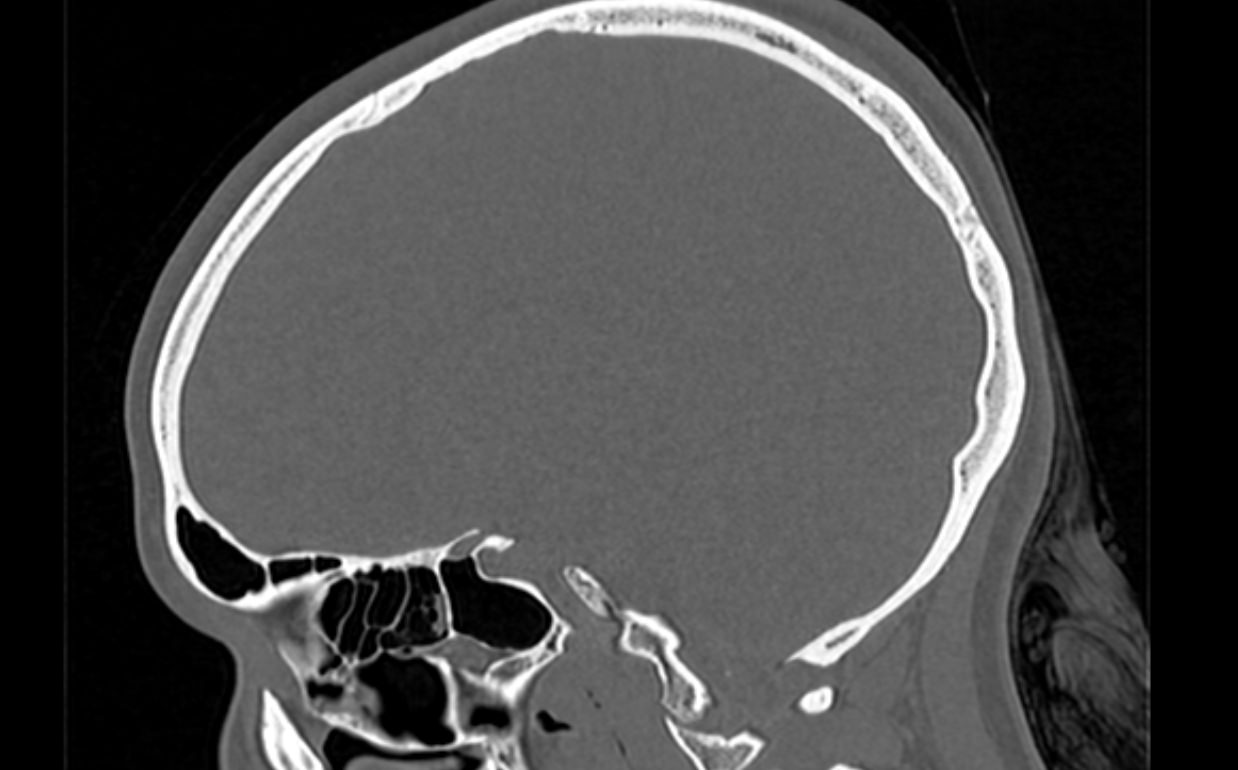

Мультиспиральная компьютерная томография является наилучшим методом диагностики патологии костей черепа. В основе методики лежит использование рентгеновского излучения с последующей цифровой обработкой полученных данных и получения трехмерных реконструкций изображений.

Костная ткань отличается высокой плотностью и способна в большой степени поглощать рентгеновские лучи. Поэтому на послойных снимках, полученных при проведении мультиспиральной КТ черепа можно детально рассмотреть свод черепа, кости лица, основание черепа. Это позволяет с наибольшей точностью визуализировать различные объемные образования, такие как остеомы, дифференцировать фиброзную дисплазию или костные метастазы. Преимуществами методики КТ является отличная визуализация костных структур, быстрота выполнения процедуры и доступная цена. Все это делает КТ незаменимой при диагностике травматических повреждений (например переломов основания черепа или орбит), аномалий развития, при планировании оперативных вмешательств.